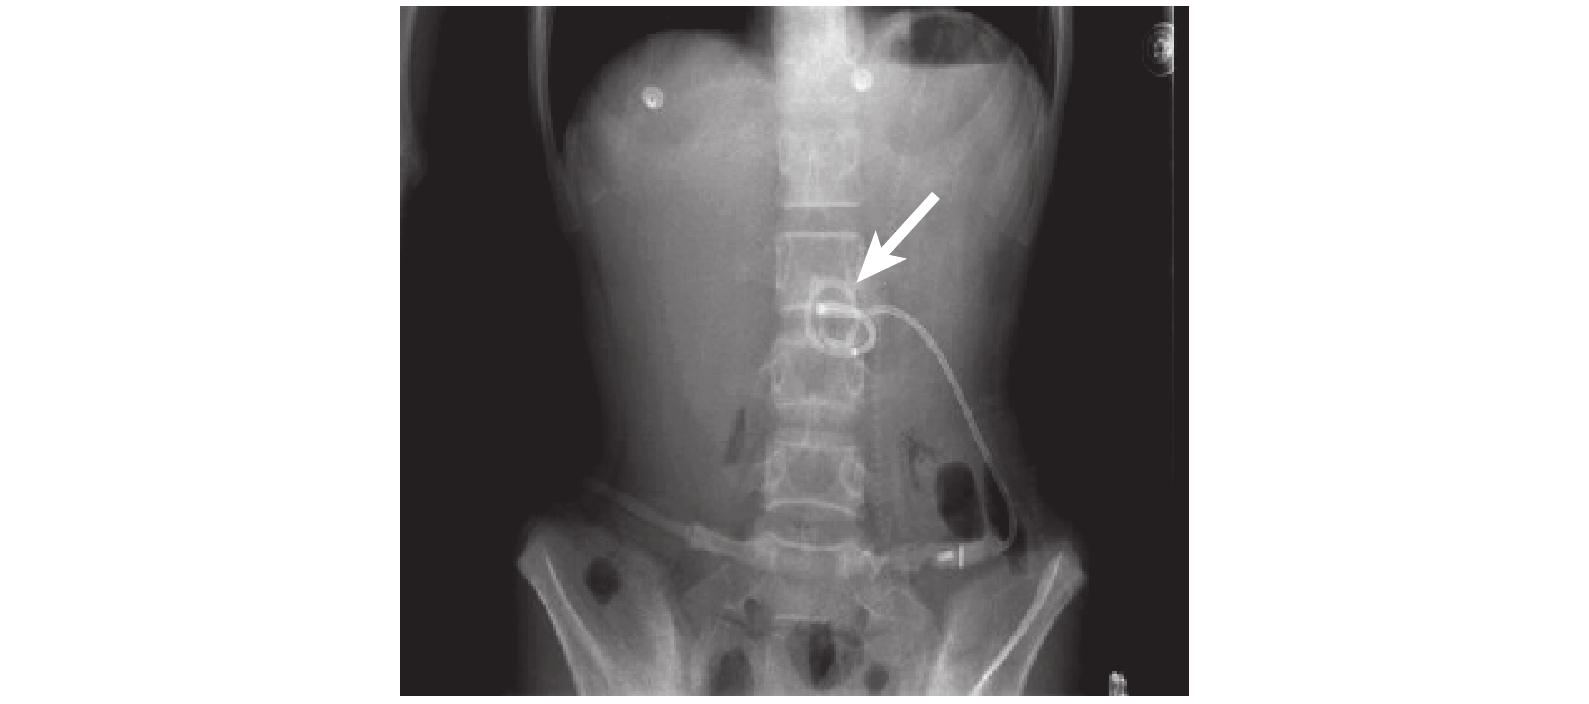

入院后評估患者的身體狀況:① 經早期治療后,生命體征保持平穩;② 腹部體征無加重,范圍也無擴大;③ 腹腔內無活動性出血;④ 無其他臟器合并傷。因此,予以禁飲食,持續胃腸減壓,質子泵抑制劑抑制胃酸分泌,靜脈補充水、電解質,廣譜抗生素抗感染,靜脈泵入生長抑素抑制胰液分泌,并行腸外營養支持,生大黃泡水后低壓灌腸,腸道功能恢復后早期經鼻空腸營養管行腸內營養支持,然后行經皮胰周穿刺置管引流(圖 3)。